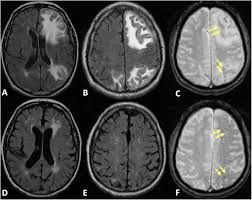

The idea that obstructive sleep apnea might be linked to cerebral microbleeds sends a silent chill down your spine: breathing poorly while you sleep and simultaneously leaving tiny, almost imperceptible traces of blood in your brain. A JAMA Network Open study in Korea, involving more than 1,400 adults, found that those with moderate to severe sleep apnea had twice the risk of developing cerebral microbleeds (CMBs) after eight years.